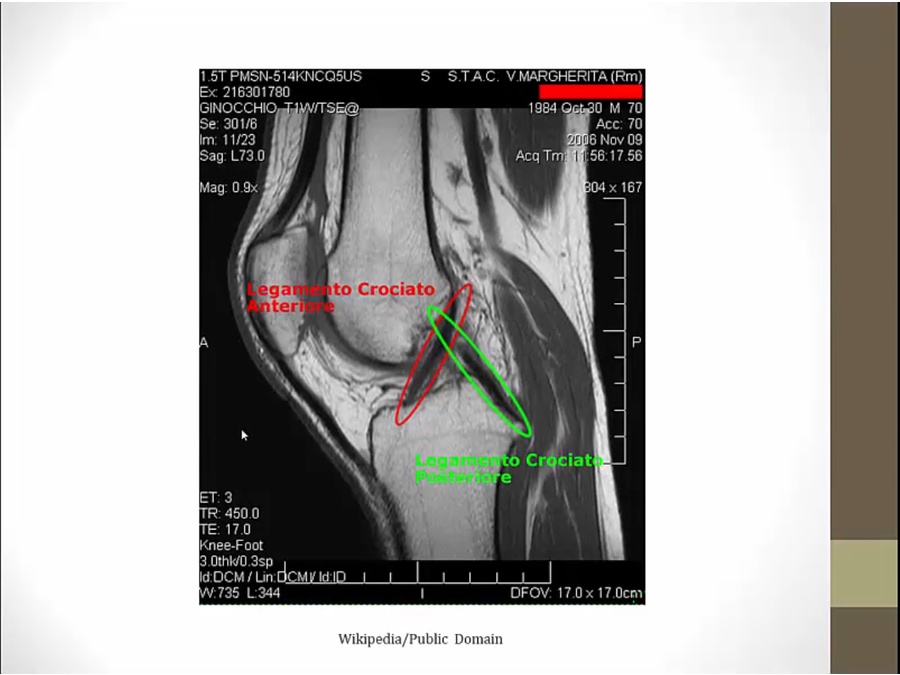

ACL

PCL

left pic: black line attaching to anterior tibia (anterior cruciating)

right pic: black line attach to posterior tibia (posterior cruciating)